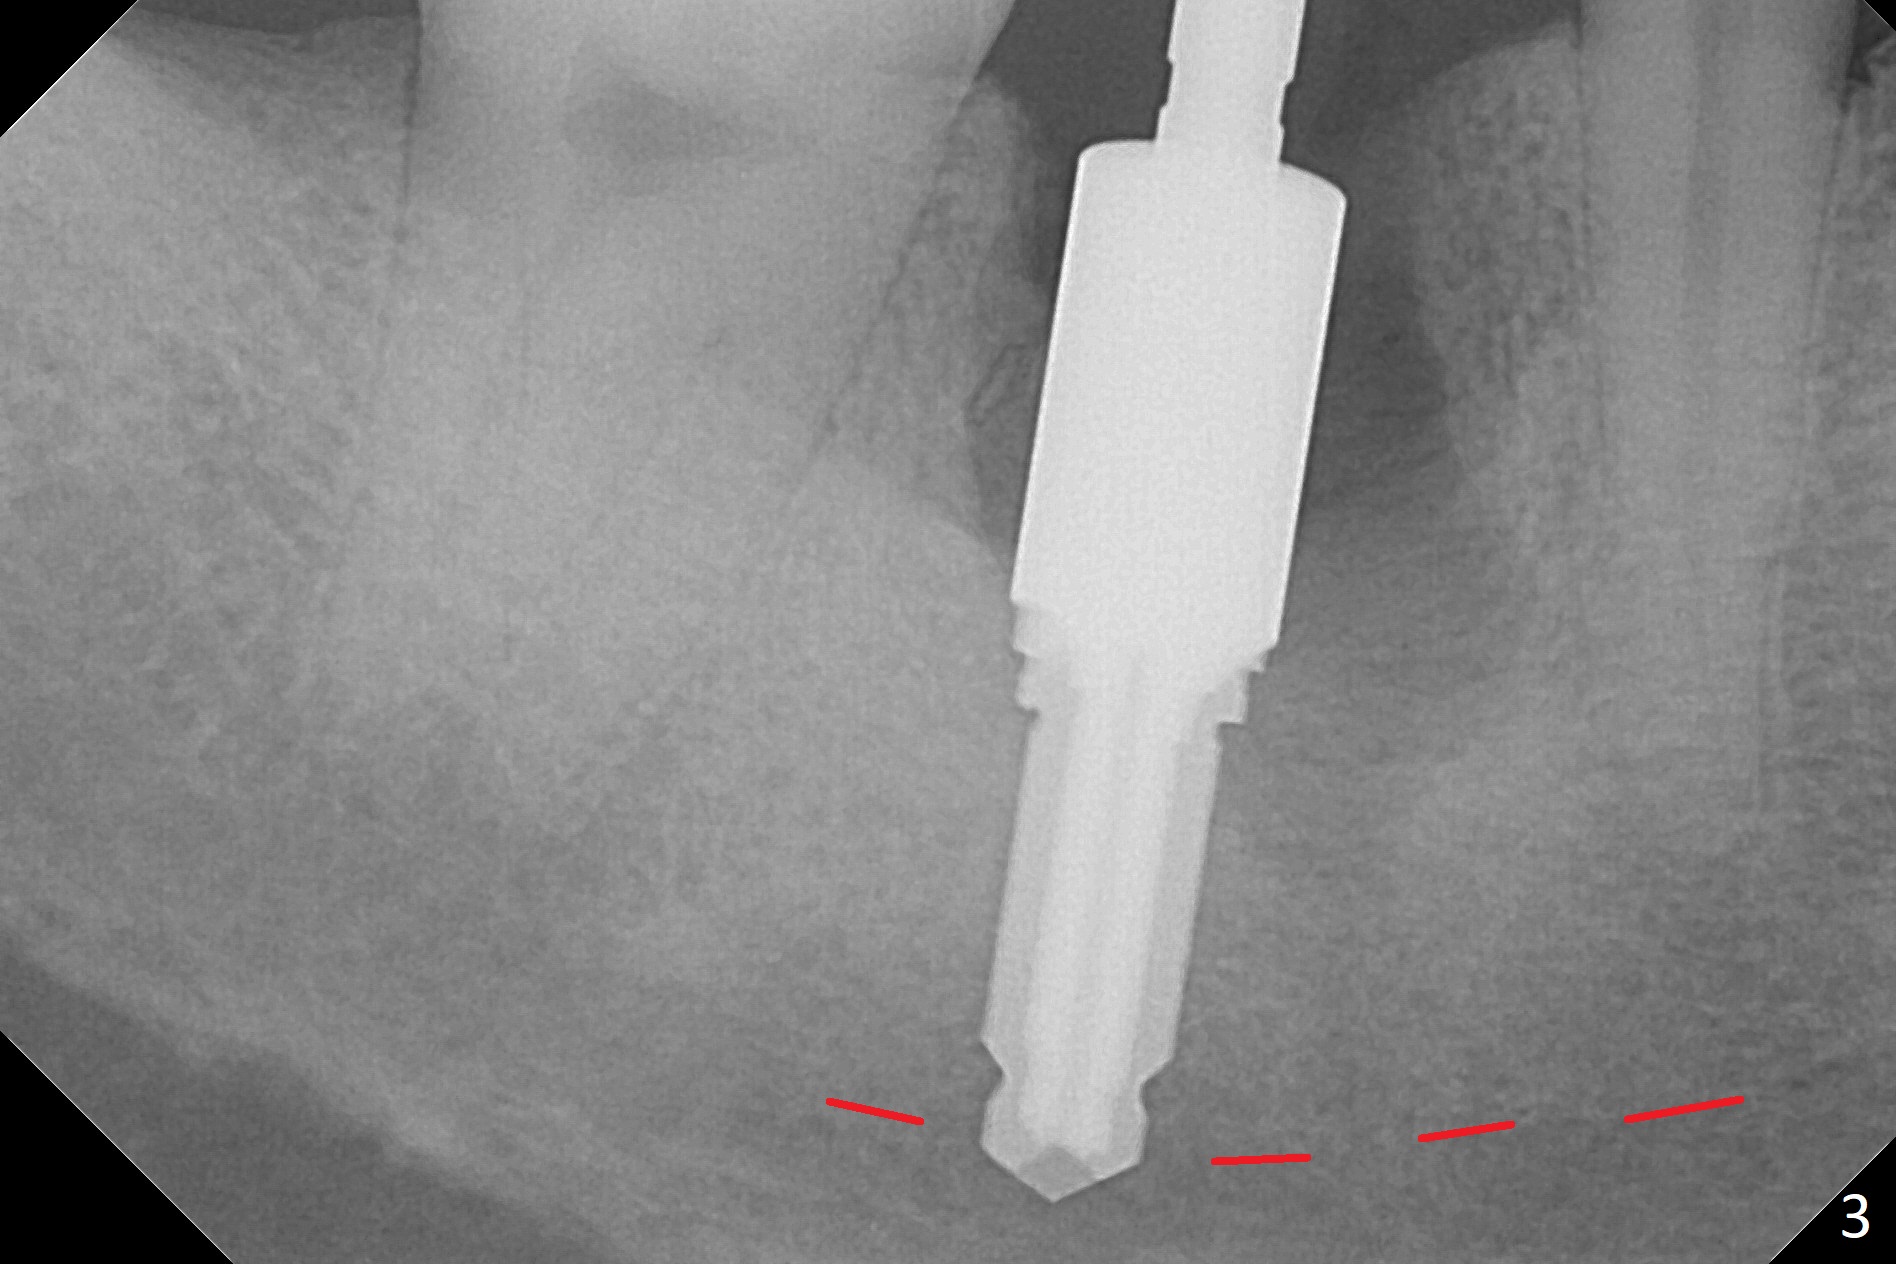

After the tooth #30 is extracted, the socket is 18 mm deep and the lingual plate is 4 mm tall. With hemorrhage, visibility of the socket, especially the bottom, is poor. The septum is almost completely defective. Following removal of the most buccal portion of the septum, osteotomy is initiated as buccal as possible, but it is mesial (Fig.1). In spite of effort to move the osteotomy distal, the osteotomy remains mesial and superficial (Fig.2 with 5 mm tap drill). Pain control is poor with infiltration. It appears that the smaller osteotomy (Fig.2 yellow line) may have extended close to the superior border of the Inferior Alveolar Canal (red line). It appears that there is 8.5 mm bone distal with ~ 2 mm clearance. After mandibular block, a new osteotomy is made distal; when a 3.8 mm drill is being used, there is hemorrhage from the osteotomy with apparent violation of the Canal integrity (Fig.3,4). But hemostasis is achieved with gauze pressure. A 5x13 mm implant is placed superficially (Fig.5) with a trace of the previous osteotomy (yellow line) and deep space created by the mesial osteotomy (*). Apparently the pathological and iatrogenic defects are filled with allograft (Fig.6 *). Guided surgery could have avoided the mesial osteotomy.